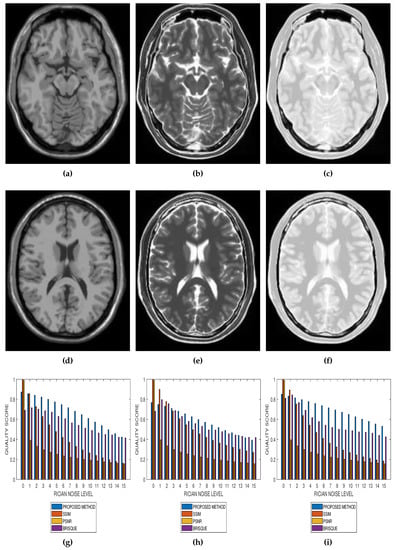

Results from comparative performance evaluation of the proposed method with SSIM, PSNR and BRISQUE are displayed in Figure 10 and Figure 11, for real and simulated MRI data, respectively. Figure 10a–d are quality predictions on T2, T1, breast and cardiac MRI slices for Rician noise levels from 0 to 15. The images in the first, second and third columns of Figure 11 are sample MRI images from simulated T1, T2 and PD MRI volume data. Quality predictions corresponding to each MRI volume data, for Rician noise levels from 0 to 15, are the plots in the last row of Figure 11. For all the quality metrics, there is a general trend of decreasing quality score with increasing noise level. Table 1, Table 2, Table 3 and Table 4 are the subjective evaluation results from the comparative performance of our proposed method with SSIM, PSNR and BRISQUE quality metrics.

Figure 11.

Comparative performance evaluation of the proposed method with SSIM, PSNR and BRISQUE quality metrics using 15 slices in (a,d) T1, (b,e) T2 and (c,f) PD simulated MRI volume data from McGill University BrainWeb (g–i).

There is no doubt that SSIM, PSNR and BRISQUE are popular and efficient quality evaluation techniques. The comparative performance evaluation results displayed in Table 1, Table 2, Table 3 and Table 4 as well as Figure 10 and Figure 11 reveal their limitations and add to the growing calls for application-specific quality metrics. At lower noise levels, current techniques provide an inaccurate estimate of perceptual quality. This is expected for SSIM and PSNR as their predicted quality score is based on noise level and with reference to an assumed ideal image. The no-reference BRISQUE performed better than SSIM and PSNR. However, inaccurate estimation of noise, particularly at lower noise levels in T2, T1 and Breast MRI, was evident in BRISQUE. This can be attributed to training data extracted from images corrupted by Gaussian noise rather than the Rician noise present in MRI images. The proposed method has the lowest margin between a predicted quality score and the corresponding score assigned by human observers. Furthermore, it has the highest perceptual quality discrimination for different noise levels. For these reasons, we can say that the proposed method demonstrates superior performance over current techniques.